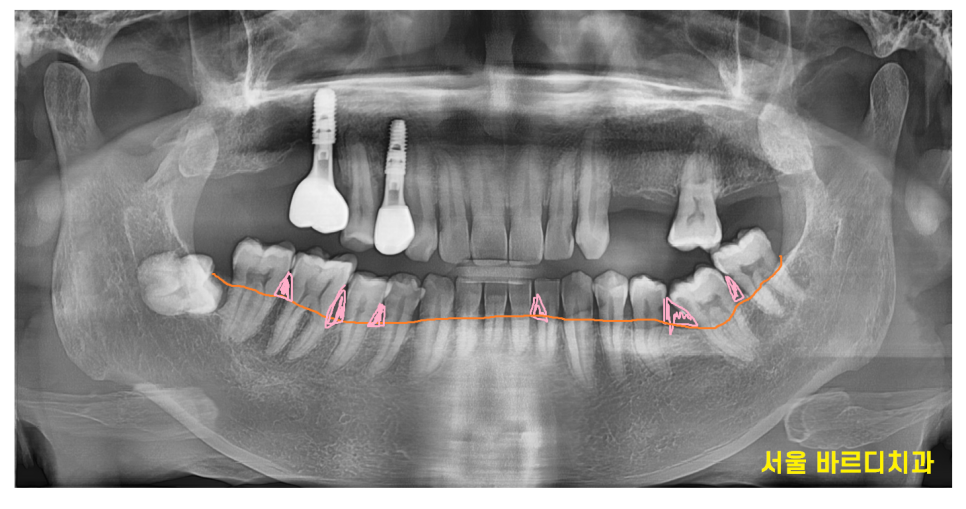

잇몸이 내려가면서

치아와 잇몸 사이 공간에 틈이 커지기도 하고요~

- 노화로 인한 잇몸 내려감

노화로 인해 치아가 조금씩 이동하거나

잇몸이 약해지면서 간격이 벌어져 음식물이 더 자주 끼게 됩니다!

치아가 길어보이는 것도 잇몸이 내려가

치아 뿌리가 드러나면서 그렇습니다!!